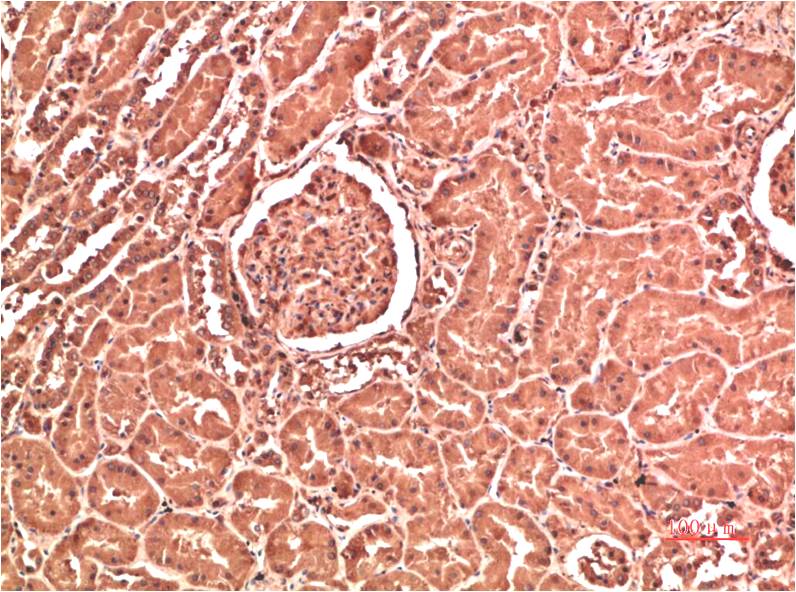

| Product Name: | Collagen IV Mouse Monoclonal Antibody(5E10) |

| Recommended dilutions: | IHC: 1:100-200 |

| Specificity: | The antibody can detects endogenous Collagen IV proteins. |

| Alternative Names: | BSVD, COL4A1, collagen type IV alpha 1 |